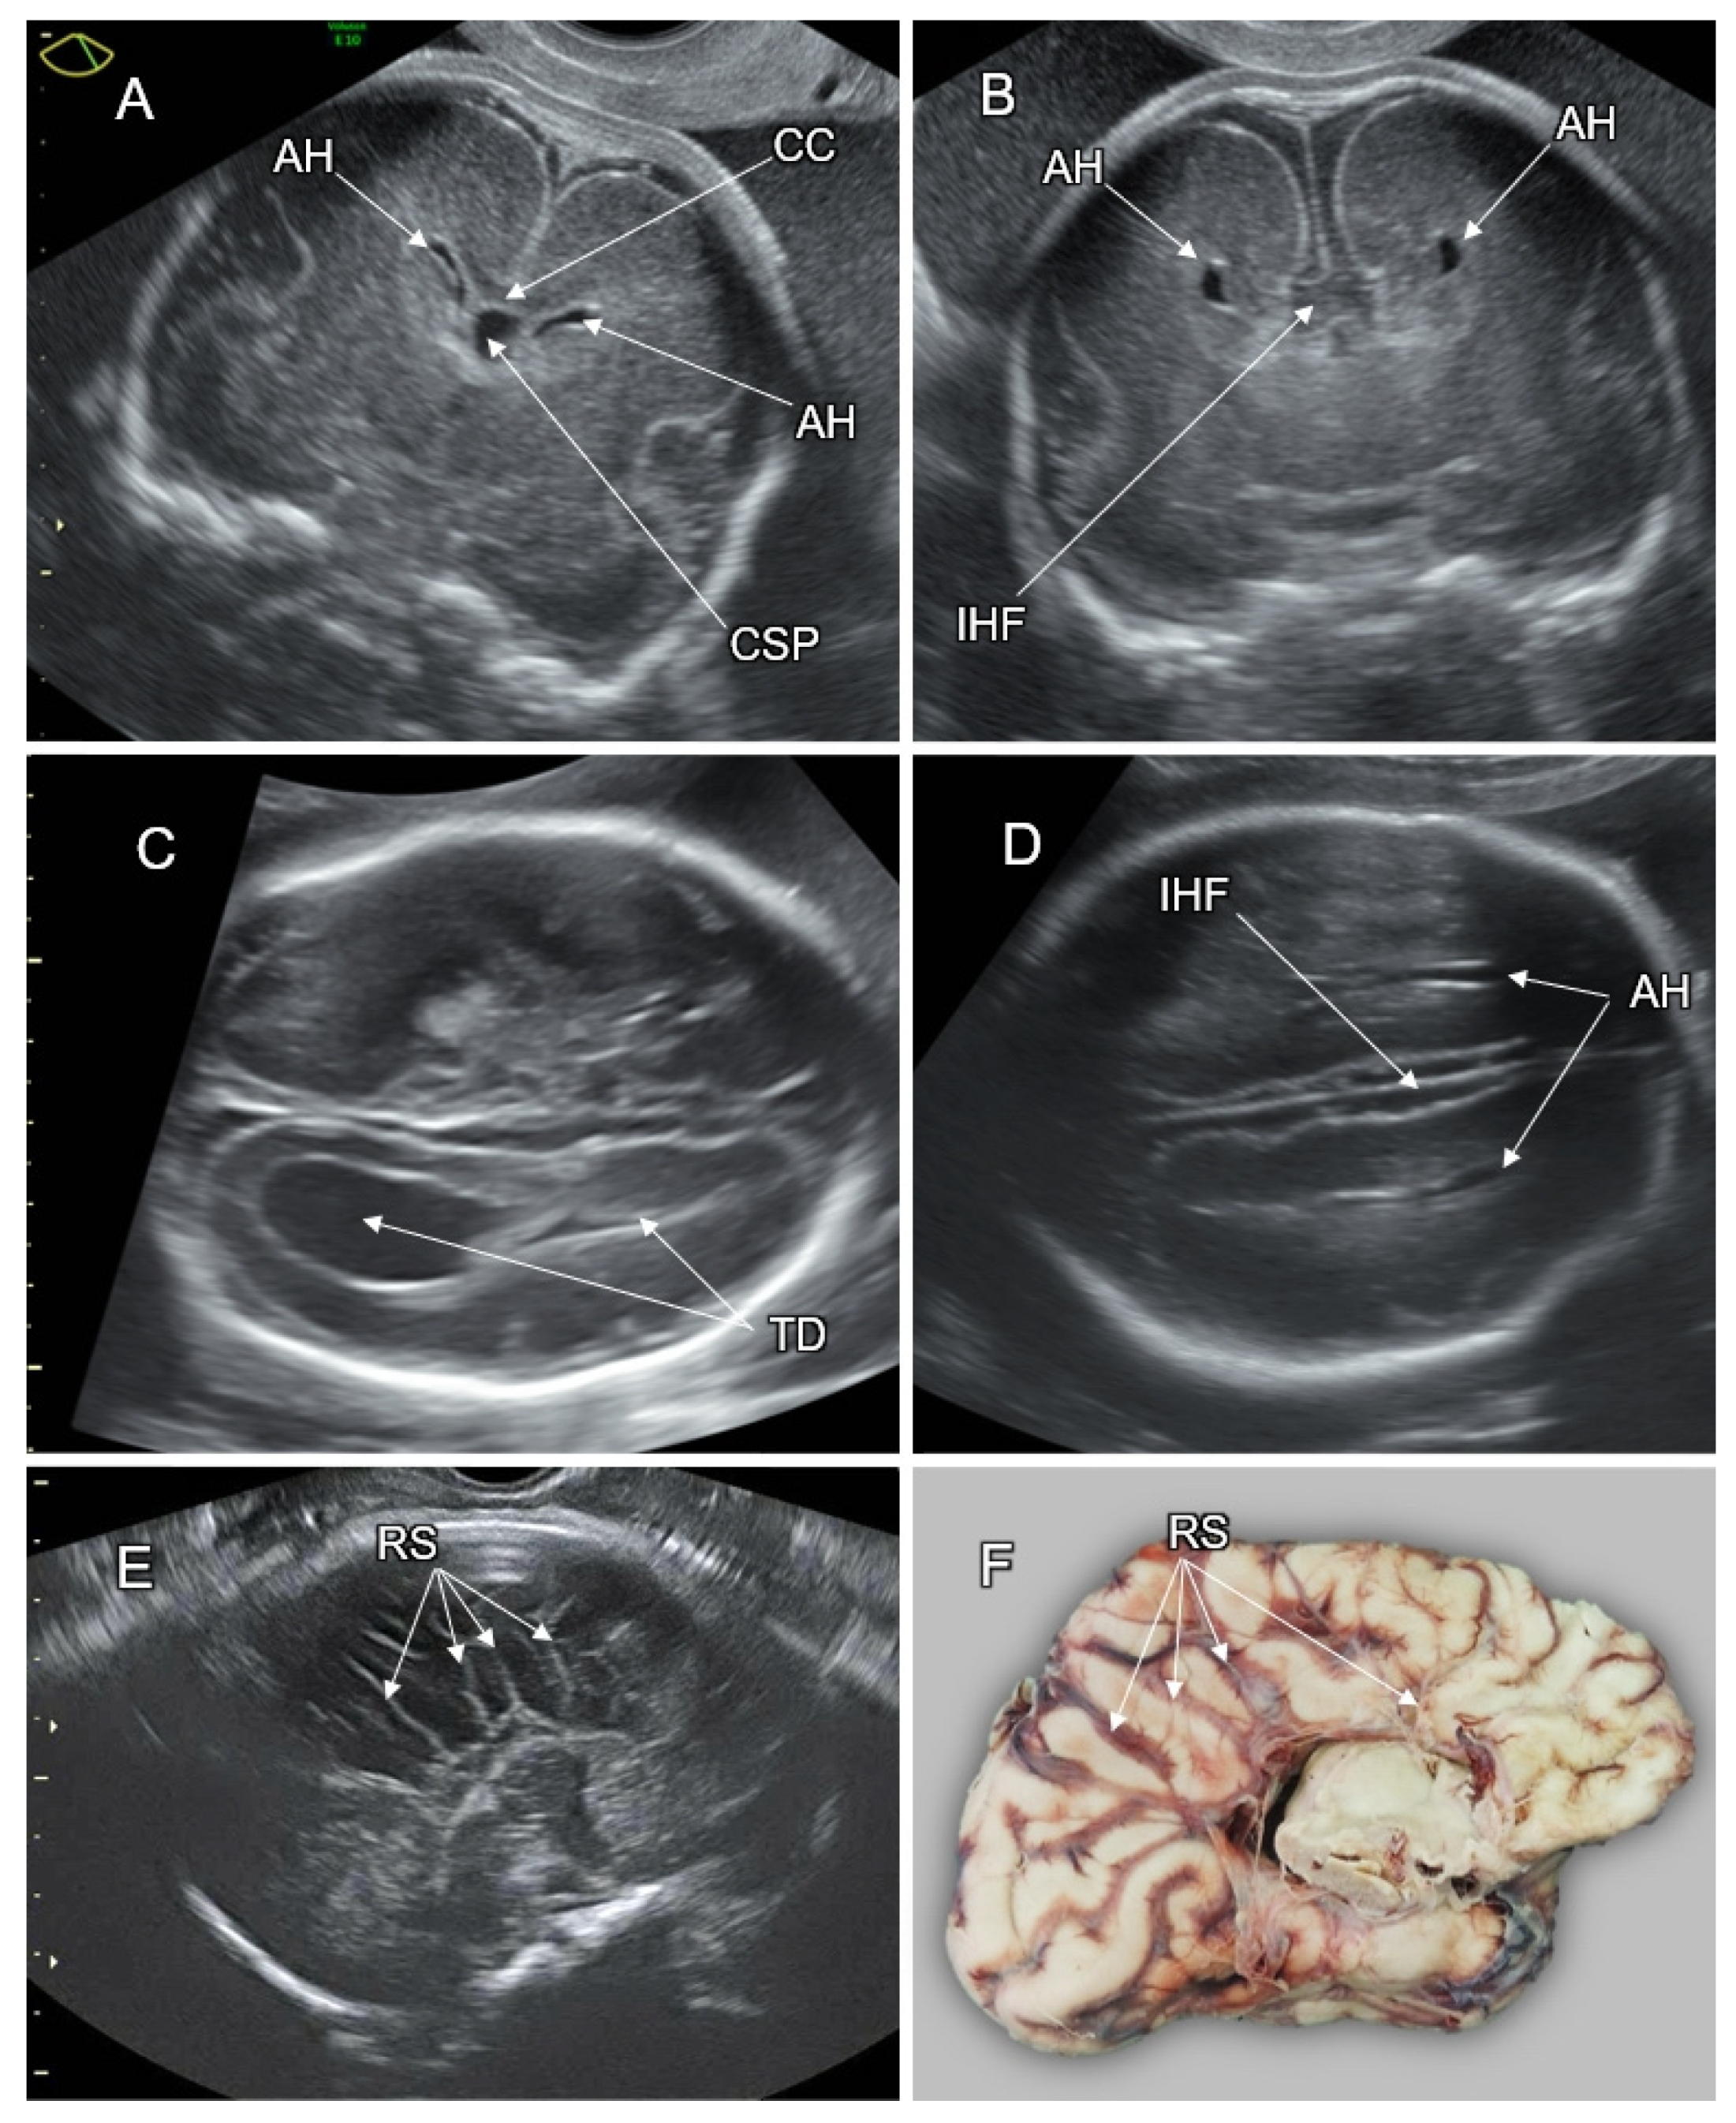

5. Disorders of the Corpus Callosum (DCC)